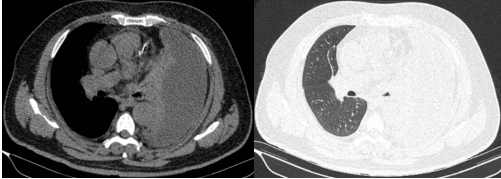

历经4小时鏖战,手术团队成功拆除"定时炸弹"。术后第二天,患者体温即开始逐渐下降,后续继续全身应用抗生素、胸腔灌注药物、控制血糖、营养支持等综合治疗,患者病情迅速好转,复查肺CT恢复良好,患者对治疗效果表示满意。